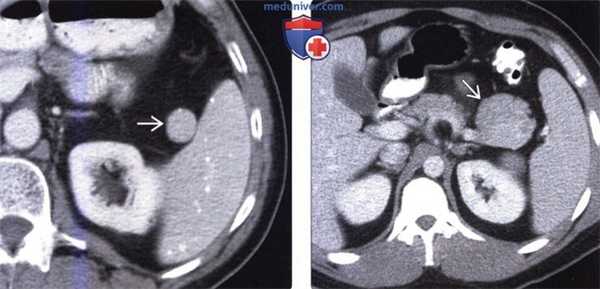

(Слева) На аксиальной КТ с контрастным усилением у пациентки, страдающей раком молочной железы, определяется метастаз в селезенке. Выявлены также несколько метастазов в печени (не продемонстрированы). Согласно результатам большинства исследований, рак молочной железы чаще всего обусловливает вторичное поражение селезенки.

(Справа) На аксиальной КТ с контрастным усилением определяется гиперваскулярное объемное образование в селезенке, которое было верифицировано как метастаз карциноидной опухоли желудка. Также опухоли селезенки необходимо дифференцировать с новообразованиями хвоста поджелудочной железы или других органов, располагающихся в поддиафрагмальной области слева.